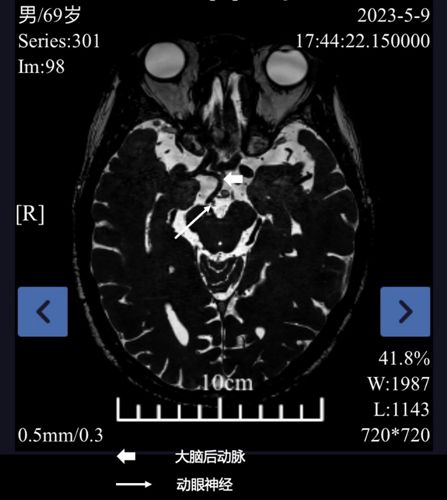

王知非教授接诊后,考虑患者可能是右侧动眼神经麻痹,但病因不明。收入院后,请影像科、眼科、神经内科等多学科会诊讨论。团队综合分析患者的病情后,为患者行颅脑薄层神经和血管扫描(着重追踪动眼神经),最终确定病因为:右侧动眼神经受到了走行异常的大脑后动脉压迫。